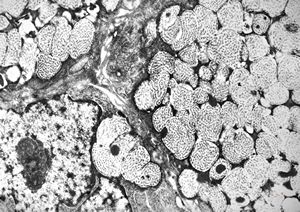

F, 24y. | molluscum contagiosum … virions

F, 24y. | molluscum contagiosum

F, 24y. | molluscum contagiosum

F, 24y. | molluscum contagiosum … virions